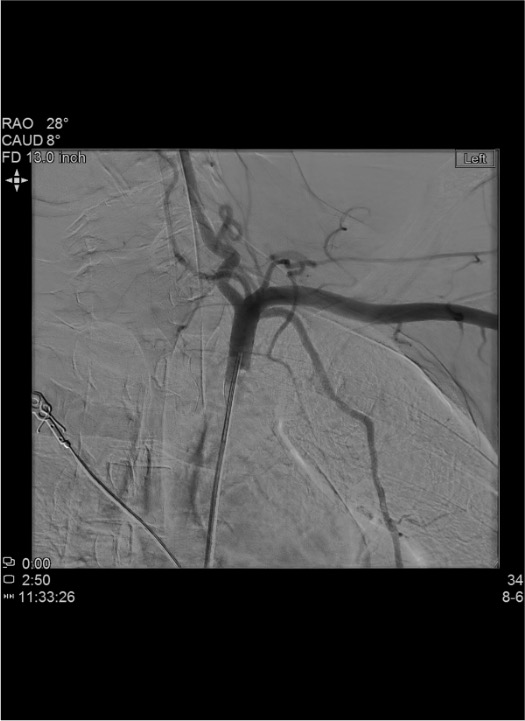

- On angiogram: identify injury as extravasation (active bleed), contained PSA (delayed filling), intimal flap (linear lucency), or abrupt cutoff (occlusion)

- Run angiographic series through to venous phase to identify AV fistula (early venous opacification)